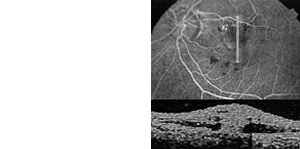

Amblyopiescreening bei Säuglingen und Kleinkindern

Die automatische Infrarot-Videorefraktion ermöglicht die sekundenschnelle, dynamische, binokulare Messung von Fehlsichtigkeiten und kleinwinkligem Schielen aus einem Meter Entfernung. Diese Untersuchung ist nicht-invasiv;

der Säugling muß zunächst nicht getropft werden.